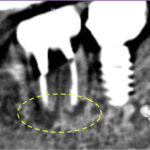

元々入っていた銀歯が脱離し、内部で虫歯が確認できる状態でした。レントゲンでは、歯髄(歯の神経)に近接する深い虫歯が認められ、歯髄検査の結果から、すでに歯髄壊死(神経が死んでいる状態)であると診断できました。

ラバーダムを装着し深い虫歯を除去すると、神経まで達していたことが確認できました。そのまま虫歯を完全除去し、歯の根の長さを測定後、ニッケルチタンファイルを使用して歯の内部の機械的拡大を行い、薬を入れて初回の治療は終了しました。

2回目の来院時にはほとんど痛みは消失していました。再度根の中を清掃し、根管充填・コア築造まで行い、治療は完了しました。

術後12ヶ月時点で全く痛みはなく、レントゲン画像でも問題なく治癒していたため、セラミッククラウンへ移行しました。